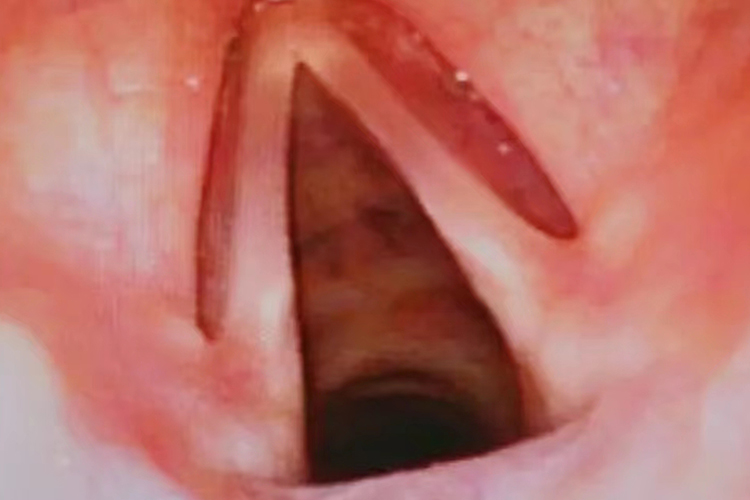

正常喉咙是由喉软骨、韧带、纤维膜喉肌和喉黏膜等共同围成的管腔。喉腔上起自喉口,与咽相通,向下经气管通支气管和肺。喉镜检查喉及喉咽左右两侧对称,梨状窝无积液,黏膜呈淡红色。